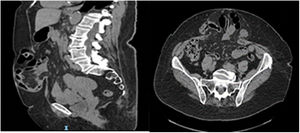

Mujer de 78 años con un índice de masa corporal (IMC) de 30,5 y antecedentes de colecistectomía a través de incisión subcostal derecha hace 42 años y hernioplastia umbilical hace cuatro años. Actualmente presenta eventración M2-3-4W2R1 (fig. 1) e índice de Tanaka de 28%, candidata a neumoperitoneo preoperatorio. Tras 72 horas de insuflación diaria de 1 litro, la paciente comienza con disnea y se realiza una radiografía abdomen-tórax, mostrando neumotórax masivo derecho (fig. 2) y requiriendo drenaje torácico e ingreso hospitalario. La paciente evoluciona favorablemente y es dada de alta al 6.° día.